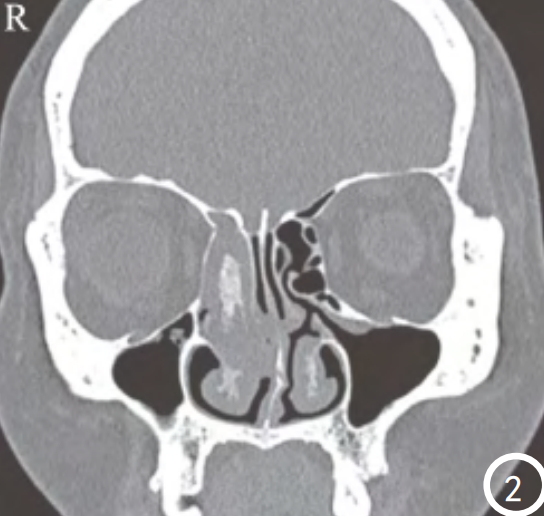

1)CT和MRI是术前预测肿瘤根蒂的关键。CT显示骨质增生、气泡征等有助于肿瘤根蒂的定位。MRI可以清楚显示病变的起源部位、生长方向、大小。(下图左CT2显示右侧筛窦骨质增厚,提示根蒂部)(下图右,MRI3现实右侧上颌窦栅栏或脑回征,提示内翻性乳头状瘤。)